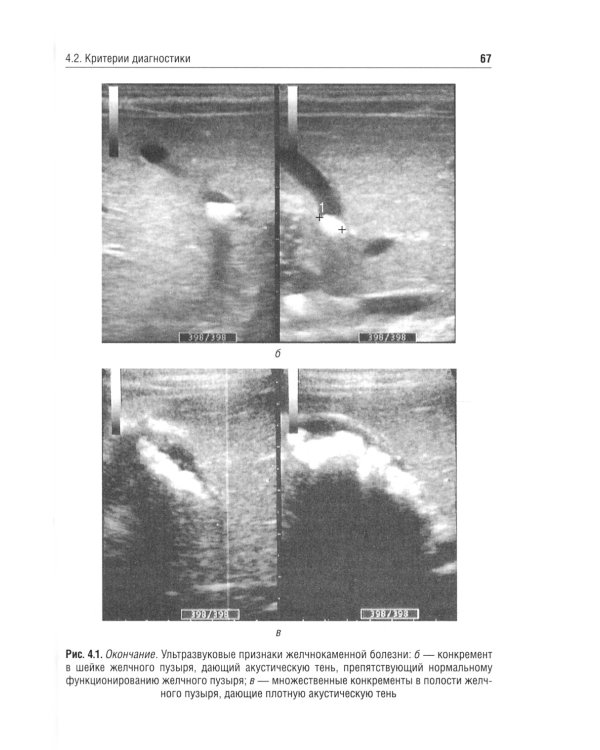

В учебном пособии рассмотрены отдельные морфофункциональные особенности билиарного тракта, вопросы физиологии желчеобразования и желчеотделения, а также представлены материалы, касающиеся диагностики и лечебной тактики дискинезий желчевыводящих путей, хронического холецистита и желчнокаменной болезни. Приведены анамнестические, клинические и дополнительные критерии диагностики, позволяющие оптимизировать диагностическую тактику, а также программы назначения лечебно-коррекционных мероприятий с учетом индивидуальных и возрастных особенностей пациента. Отражены сведения, касающиеся новых клинических вариантов течения билиарных дисфункций у детей, - диспластикоассоциированных дискинезий желчевыводящих путей. Пособие предназначено студентам медицинских вузов, а также врачам-педиатрам, гастроэнтерологам, терапевтам, врачам общей практики.| Издательство | ГЭОТАР-Медиа |